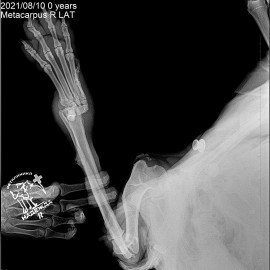

Снимки 2-3 вывих правого запястного сустава.

Снимок 4 после операции на запястном суставе.